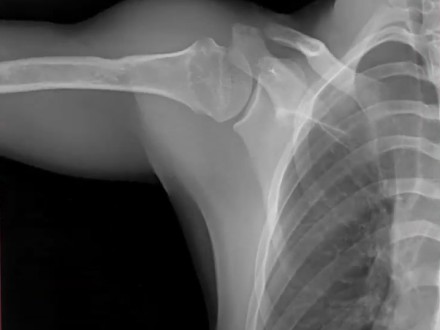

A standard X-ray provides tremendous value to a clinician for its ability to quickly provide a static image of anatomical structures. There are limitations, however, to static exams. Multiple conventional X-rays are often needed to show a joint in flexed and extended positions. A single static image cannot provide the details of how a joint moves between flexion and extension points or tell the complete story.